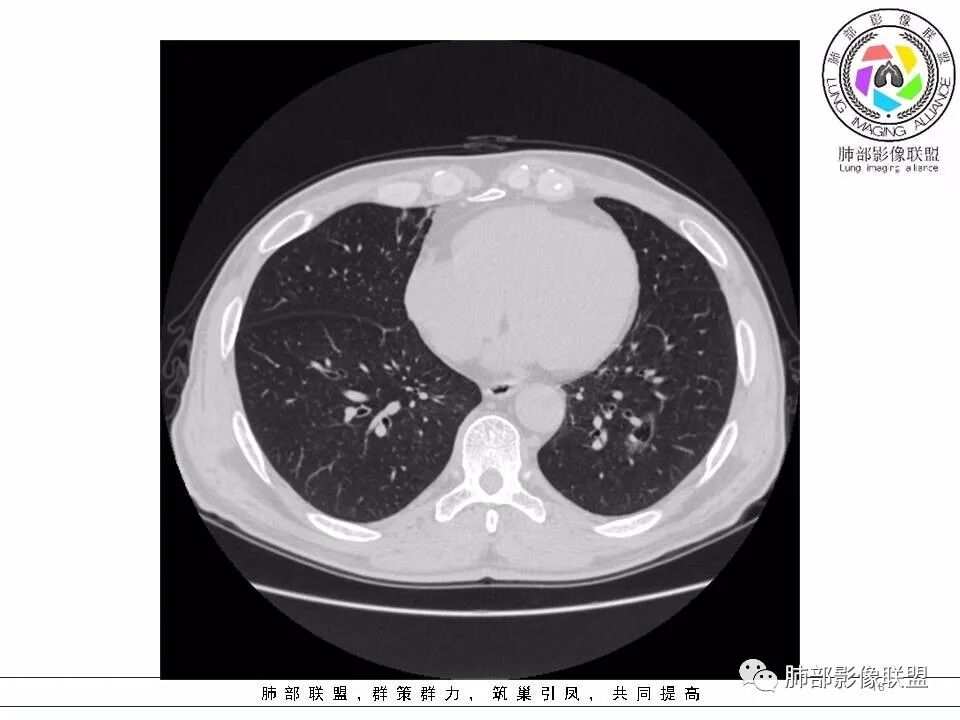

2.左肺下叶外基底段囊腔样病灶,轮廓柔和,壁厚薄不均,见壁结节。内见分隔或脊状突起。腔内见血管穿行。

这是有“故事”的囊!

3.囊壁外环以磨玻璃影,边界较清楚。

1.囊腔壁厚薄不均,壁结节,内有分隔,其内有血管穿行,指向新生物。

2.临近有边界清楚磨玻璃影,指向腺癌。